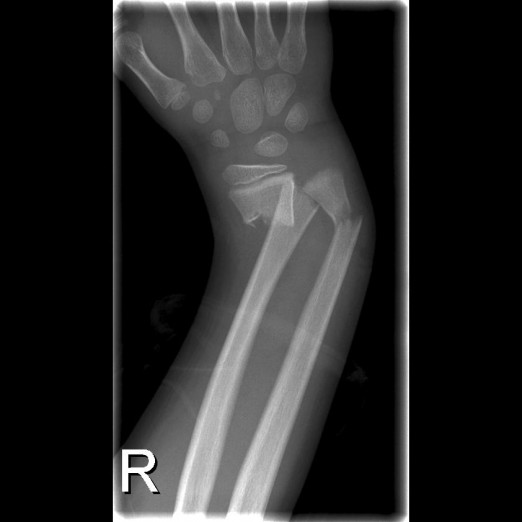

6-vuotiaan pojan rannemurtuma seurauksena reilun metrin putoamisesta. Kuva Mervi Mäyränpään arkisto.

Yksittäisenä ilmiönä tutkimuksessa nähtiin kyynär- ja olkavarsimurtumien lisääntyminen kolmanneksella samassa ajassa. Rannemurtumien yhteys alentuneeseen luuston mineraalitiheyteen on osoitettu muissakin tutkimuksissa niin aikuisilla kuin lapsilla. Jo yksittäinen murtuma voi olla merkki huonontuneesta luun laadusta. Toistuvat murtumat pienistä traumoista ja varsinkin nikamamurtumat ovat terveillä lapsilla harvinaisia.